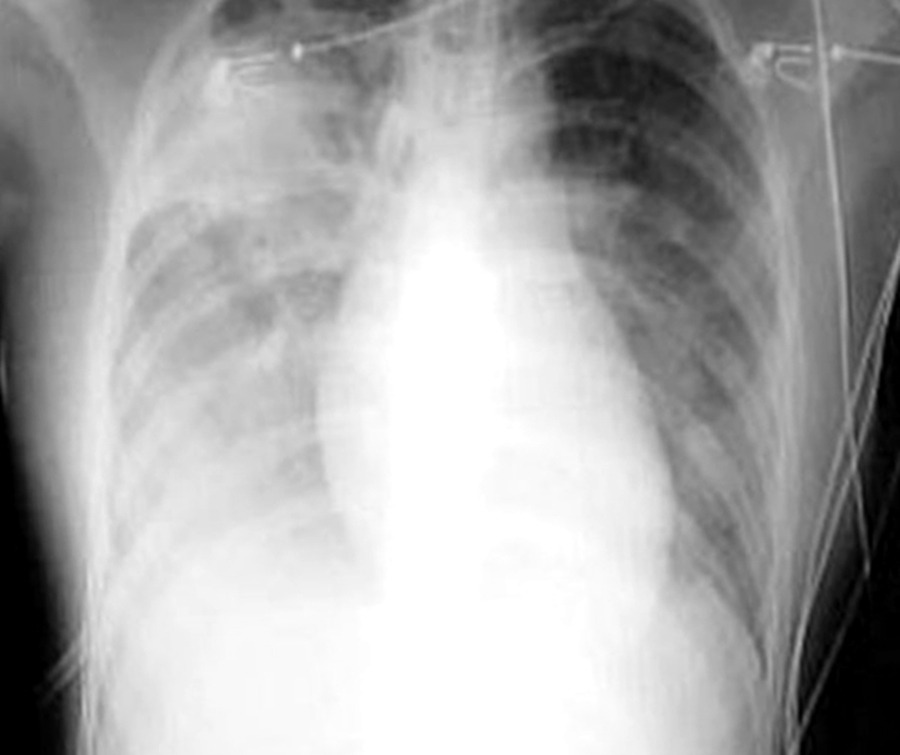

SARS_xray.jpg

상황이 악화되자 홍콩에서 근무하던 주재원 가족들의 귀국행렬이 줄을 이었다. 당시 부동산 기업에 다니던 김일도씨(가명·50)도 가족을 한국행 비행기에 태워 보냈다. “저는 홍콩에 남았지만, 가족까지 위험에 노출시킬 수 없었어요. 가족을 보내고 나서 저는 자의반 타의반 재택근무를 했습니다. 집에 갇혀 잘 때도 마스크를 쓰고 잘 정도였어요.”